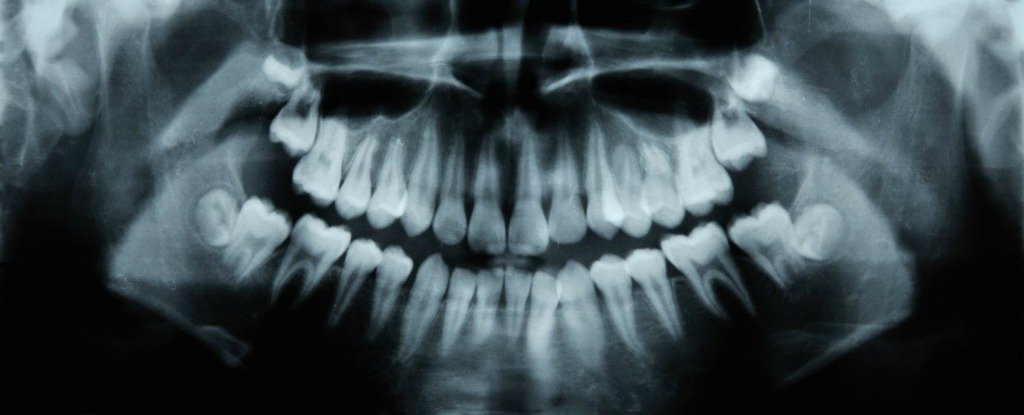

An Alzheimer's drug has been found to help teeth repair themselves in just 6 weeks